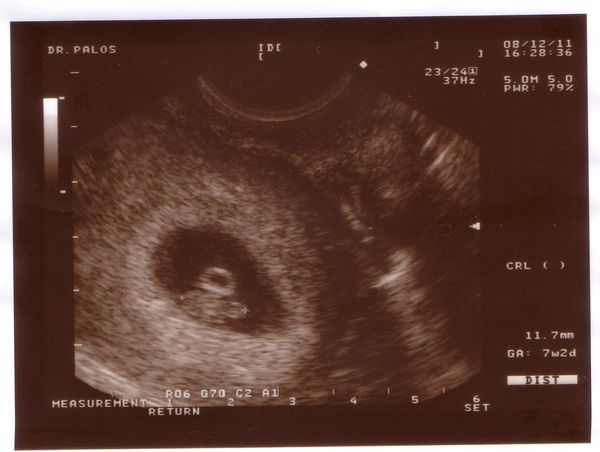

Kedden minden ok volt a dokinál. Legalábbis zárt a méhszáj és a baba is látszólag jól van. Csak a toxoplasma eredményem nem lett jó. Illetve kellett mennem tegnap egy ellenőrző vérvételre (aminek 2 hét múlva lesz eredménye) hogy kiderüljön, hogy ez egy régi fertőzésből származik vagy egy új keletű dolog. De én úgy hiszem ez egy régi dolog, mert annó cirka 10 éve volt macskánk. Úgyhogy szerintem védett vagyok. De majd 2 hét múlva kiderül minden.

Mi volt az uh-n? Na megnyugtatlak, hogy most már az egész életed egy nagy izgulás lesz. Most a terhesség miatt, ha kint lesz akkor mindig a baba miatt fogsz stresszelni (eszik, nem eszik, alszik… stb) Ha kicsi ezekért, ha nagyobb akkor meg másért.